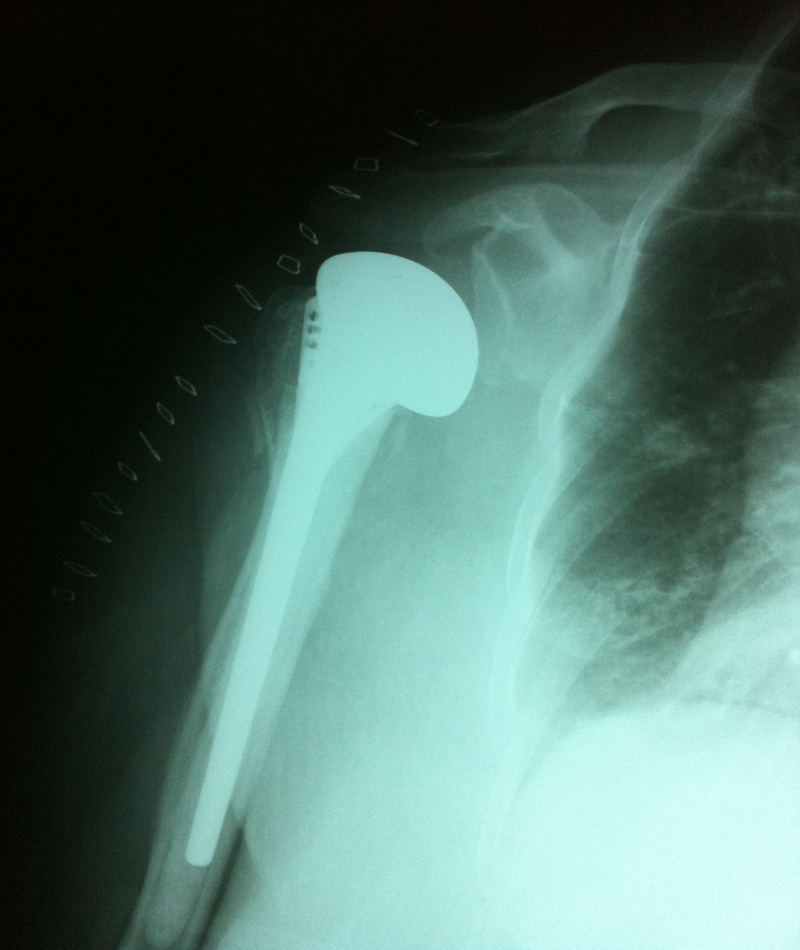

Omuz Protezi

Omuz Protezi Örnek Olgular